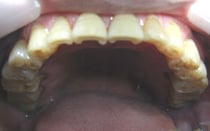

② 咬耗

過剰な歯ぎしりによって歯が磨り減ってしまう現象です。 咬耗の状態が続くと歯の表面を覆っているエナメル質が削れてしまい、内部の象牙質が露出してしまいます。

こうなるとむし歯になりやすくなったり、咬む刺激で痛みが出る場合もあります。

さらに歯が磨り減ってしまうことで歯の高さが全体的に低くなってしまうため、噛み合わせが悪くなり、場合によっては顎関節症を引き起こします。